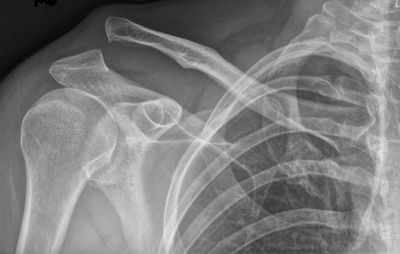

Imaging for AC Joint Injuries

Imaging tests can be helpful in diagnosing AC joint injuries and determining the appropriate treatment. Some common imaging tests for AC joint injuries include:

· X-ray: X-rays can be used to visualize the bones of the shoulder, including the collarbone and shoulder blade. They can help diagnose fractures or dislocations of the AC joint.